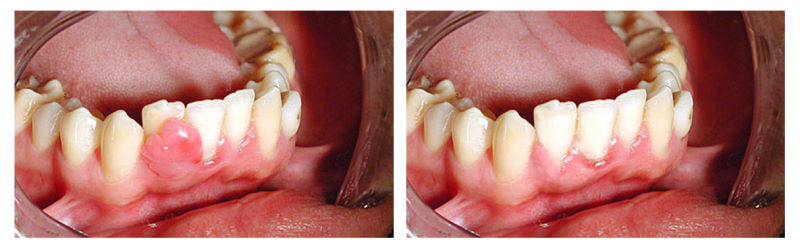

Терапевтическое лечение кисты зуба: фото до и после

Патология начинает развиваться при попадании инфекции в поврежденные околозубные ткани. На первом этапе формирования, когда диаметр не превышает полсантиметра, терапевтическое лечение кисты зуба проходит проще всего. Однако диагностировать ее достаточно сложно. Болезнь совершенно не проявляется внешне, не вызывает болевых ощущений и недомогания. Изредка можно заметить лишь незначительную припухлость десны, но ее по ошибке принимают за другие заболевания ротовой полости.

Есть шанс выявить заболевание во время рентгеновского обследования по поводу другой стоматологической проблемы. В этом случае, при допустимых размерах полости (в пределах одного сантиметра) можно применить терапевтическое лечение кисты зуба. При позднем обнаружении проблемы, чаще всего, приходится прибегать к хирургическим способам лечения. Они затрагивают целостность челюстной кости, а в некоторых ситуациях даже удаляется часть зуба.

После освобождения кистозной полости от гнойного содержимого ее заполняют специальным препаратом для повышения регенерации тканей. При терапевтическом лечении кисты зуба сначала ставится временная пломба. Для контроля эффективности пациент должен через шесть месяцев пройти на рентгенографию. Если результат удовлетворительный, корневой канал пломбируют и восстанавливают коронку. Но иногда после терапевтического лечения зуба случаются рецидивы. Поэтому важно регулярно посещать стоматолога для осмотра.